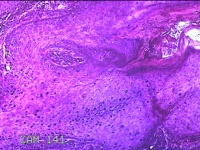

额部肿物

性别

女

年龄

32岁

临床诊断

寻常疣

一般病史

额部起疹1年,不痒。

标本名称

大体所见

灰白暗红色肿物0.7x0.5x0.2cm一个,表面光滑,切开肿物呈实性,切面灰白粉红色,质软。

图2